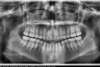

Béance traitée par gouttières

Début du traitement